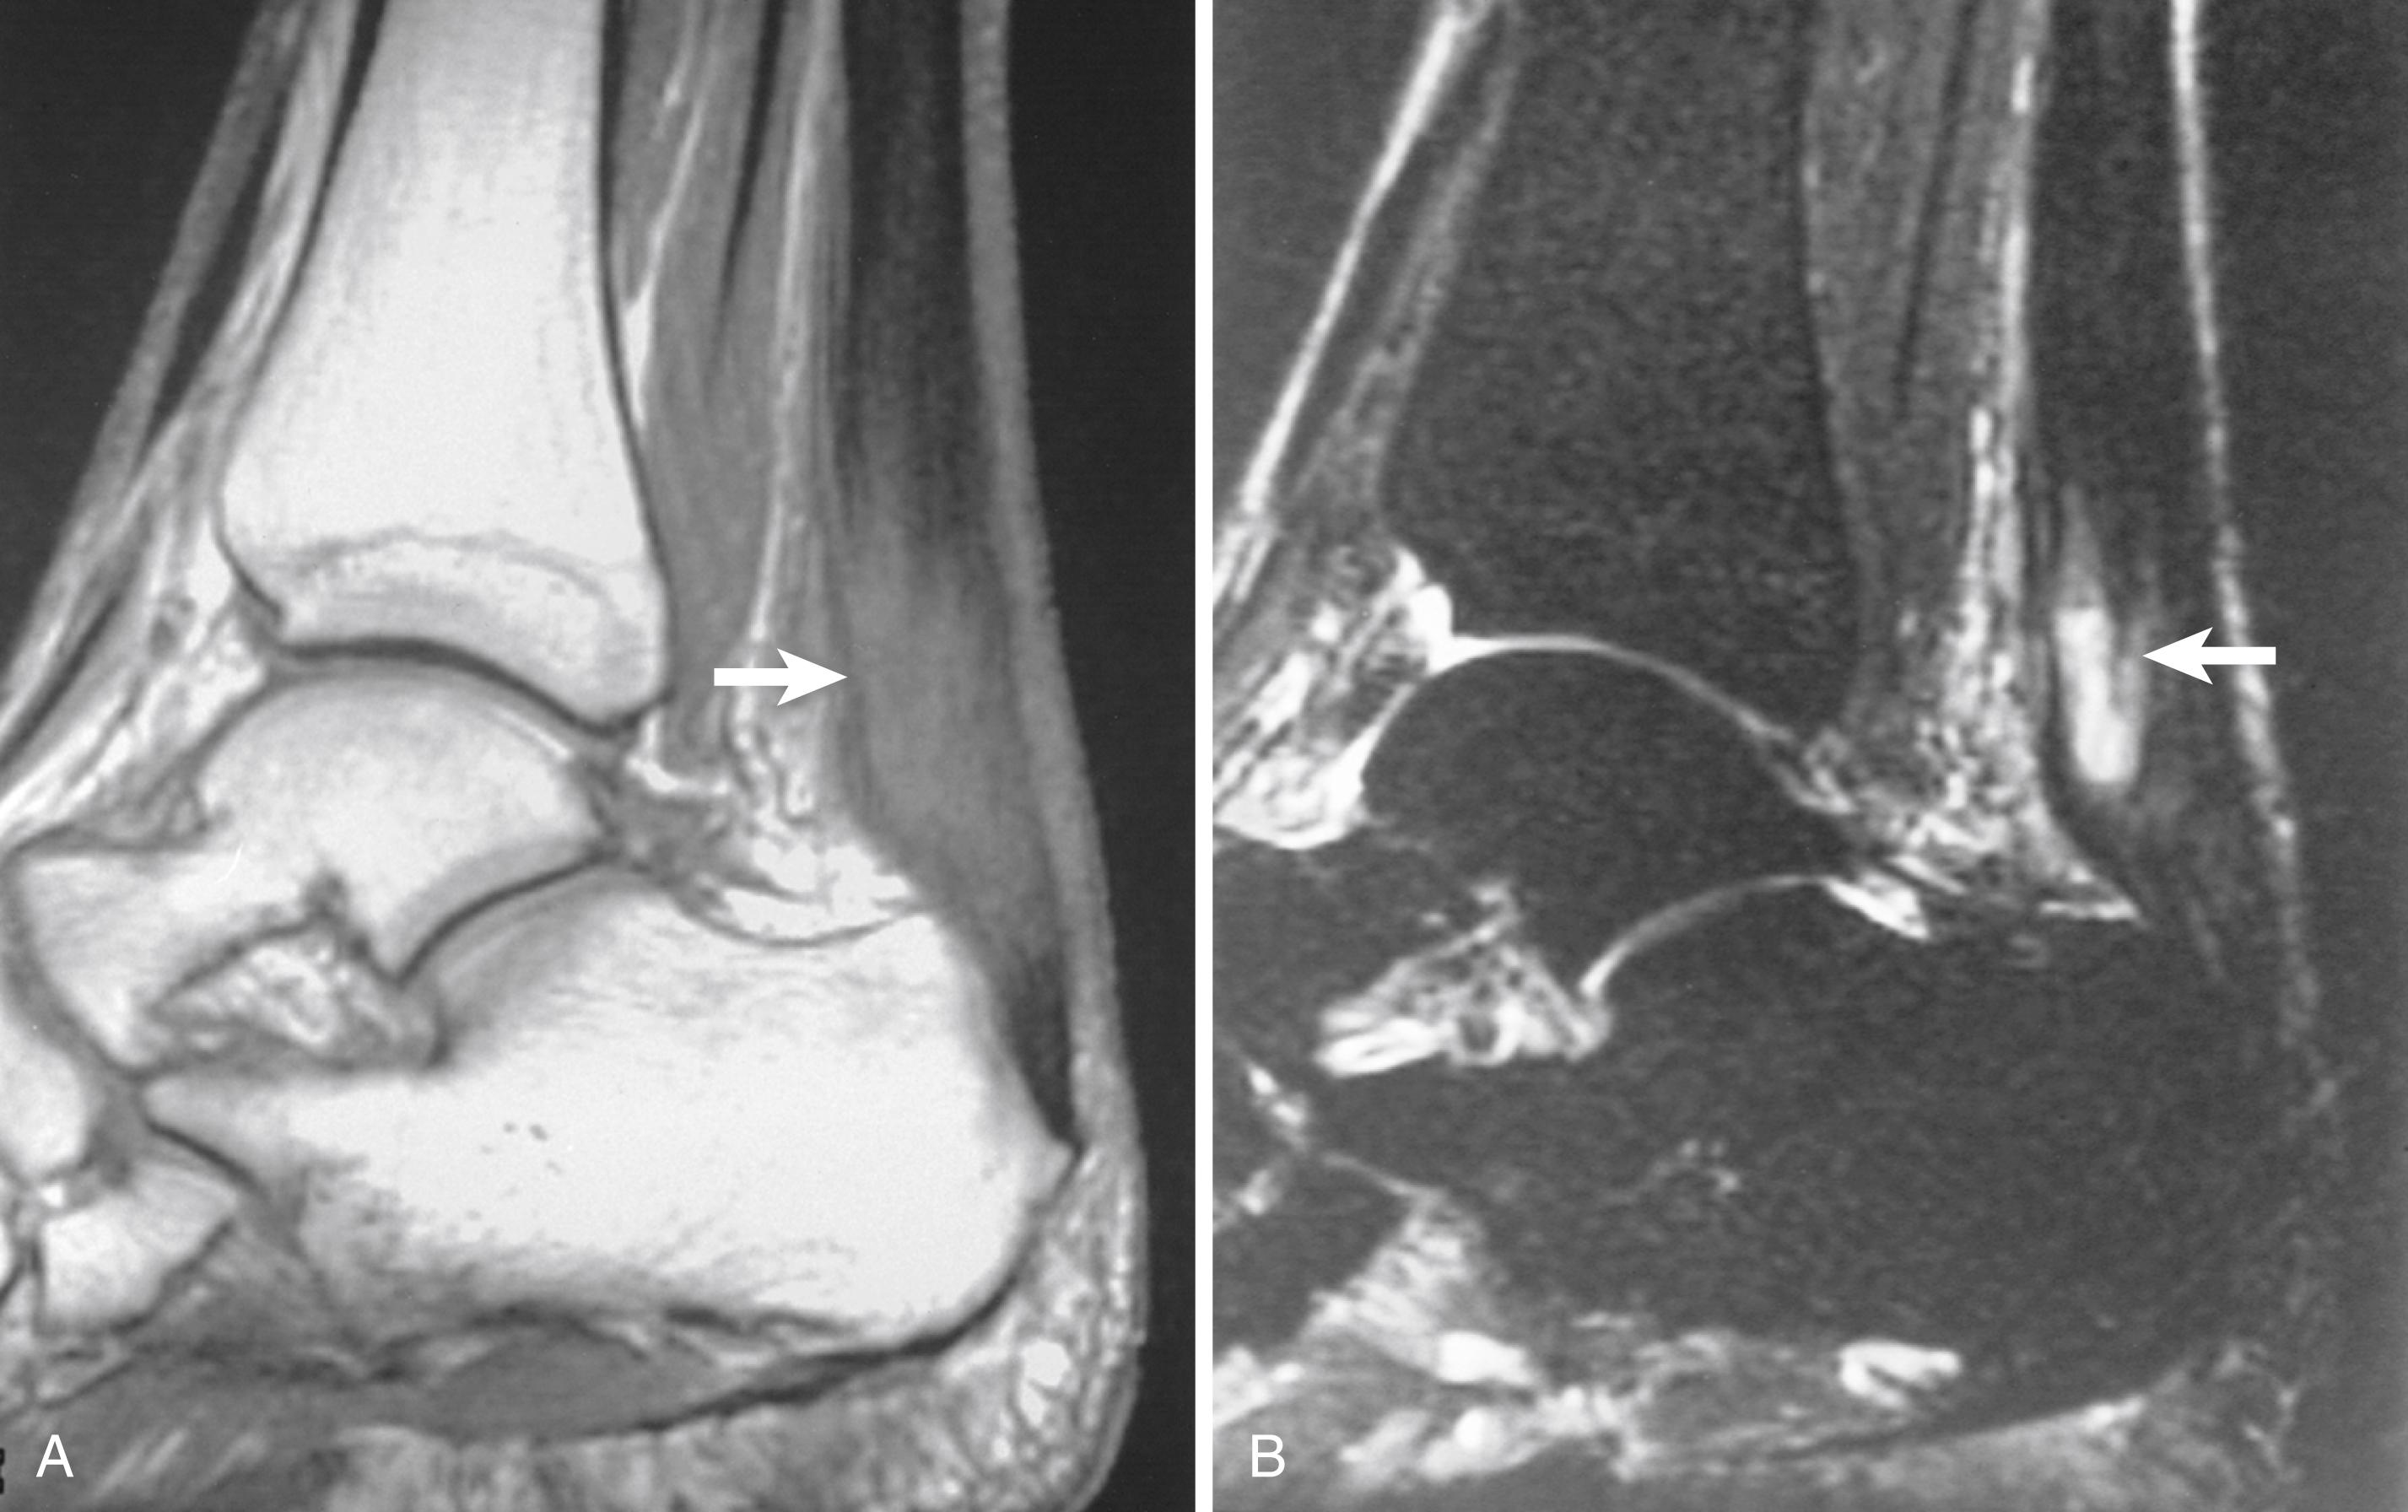

As with the rest of the skeleton, MRI is especially well-suited for evaluating occult bone pathology in the foot and ankle. MRI is often used to evaluate patients with heel pain, where the differential diagnosis includes both stress fracture and plantar fasciitis. Stress fractures are depicted as areas of marrow edema well before radiographic changes are apparent ( Fig. 2.7 ). MRI is as sensitive as bone scintigraphy while providing greater anatomic detail and specificity. The multiplanar capability of MRI is useful in assessing the ankle and subtalar joints. With high-quality imaging, excellent characterization of osteochondral lesions of the talus can be useful in surgical planning. Hepple et al. developed a classification of osteochondral lesions of the talus based on the MRI appearance. Lesion stability can be inferred by inspection of the overlying articular cartilage and the underlying osseous interface ( Fig. 2.8 ). CT plays a complementary role to MRI if osseous avulsions or tiny intraarticular calcifications are suspected. Other pathologic marrow processes such as osteonecrosis and tumors can be evaluated as well.

FIGURE 2.8, Osteochondritis dissecans of talus in college football player. A, Coronal T1-weighted image shows osteochondral fragment in medial talar dome. Loss of fat signal suggests sclerosis or fibrosis (arrow). B, Coronal fat-suppressed, T2-weighted image demonstrates fluid signal between lesion and host bone (arrowheads), indicating unstable fragment. C, Coronal fat-suppressed, spoiled gradient-echo technique reveals abnormal decreased signal (arrow) in overlying articular cartilage, indicating defect confirmed by arthroscopy.